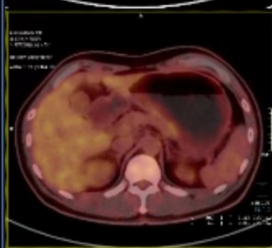

疗效评估:

2022-07至2022-10:

化疗方案:替吉奥60mg bid d1-14(q3w×4周期)

系统治疗后评估肿瘤退缩明显,经我院胃肠肿瘤MDT讨论并与患者及家属沟通后认为治疗有效,目前具备手术切除条件,拟再次手术治疗。